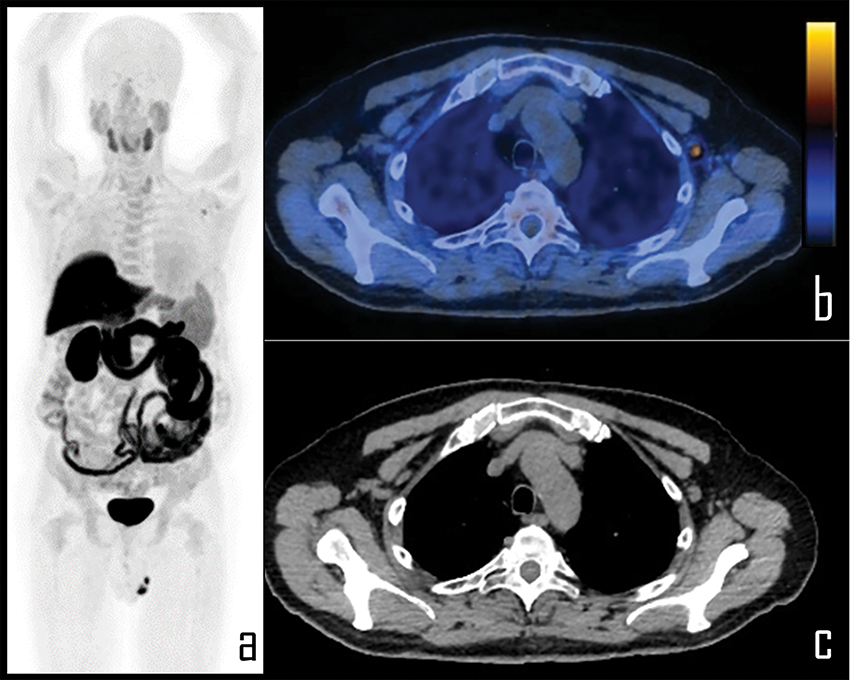

Figure 5: A 65-year-old prostate cancer patient underwent [18F]Choline PET/CT due to biochemical relapse of disease, two years after radical prostatectomy. PSA at the time of the scan was 0.4 ng/mL. Patient also underwent COVID-19 vaccine injection in the left arm 6 days before the exam.

Note: PET imaging (a) was negative for disease relapse but showed a single area of focal [18F]Choline uptake in the left axilla, corresponding to a 1 cm wide, ovoid lymph node, displayed in axial PET/CT view (b), with fatty hilum detectable in the axial, co-registered low dose CT (c). This lymph node was considered as reactive, following vaccine administration; SUVmax was 2.3.